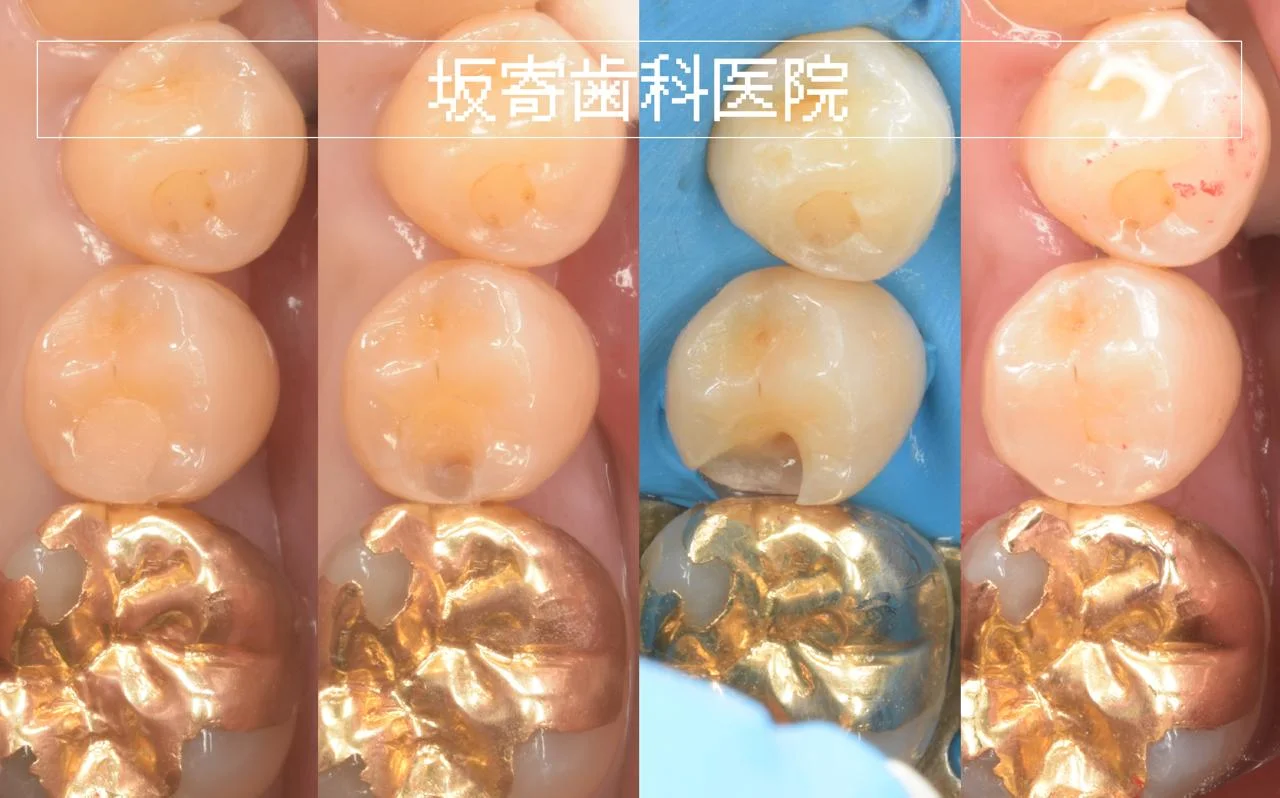

セラミックインレー破損の再治療|右下6をダイレクトボンディングで修復した症例(40代女性)

以前に入れた右下6のセラミックインレーが欠けたことをきっかけにご相談いただいた症例です。修復物の下は大きく進行していない一方で、後ろの歯との間にむし歯がみられたため、必要最小限の除去後、ラバーダム防湿下でダイレクトボンディングにて再治療しま…

歯をできるだけ残すむし歯再治療|ダイレクトボンディング症例(右上6・40代男性歯科医師)

右上6のむし歯再治療(旧CR下のむし歯)をダイレクトボンディングで修復。防湿と形態(豊隆)に配慮し、食片が入りにくい形を目指しました。

メタルインレー除去後のダイレクトボンディング|右上7|30代男性

右上7の違和感が気になる患者さんに、金属インレー除去後のダイレクトボンディングで自然な形態と色調を目指して修復した症例です。